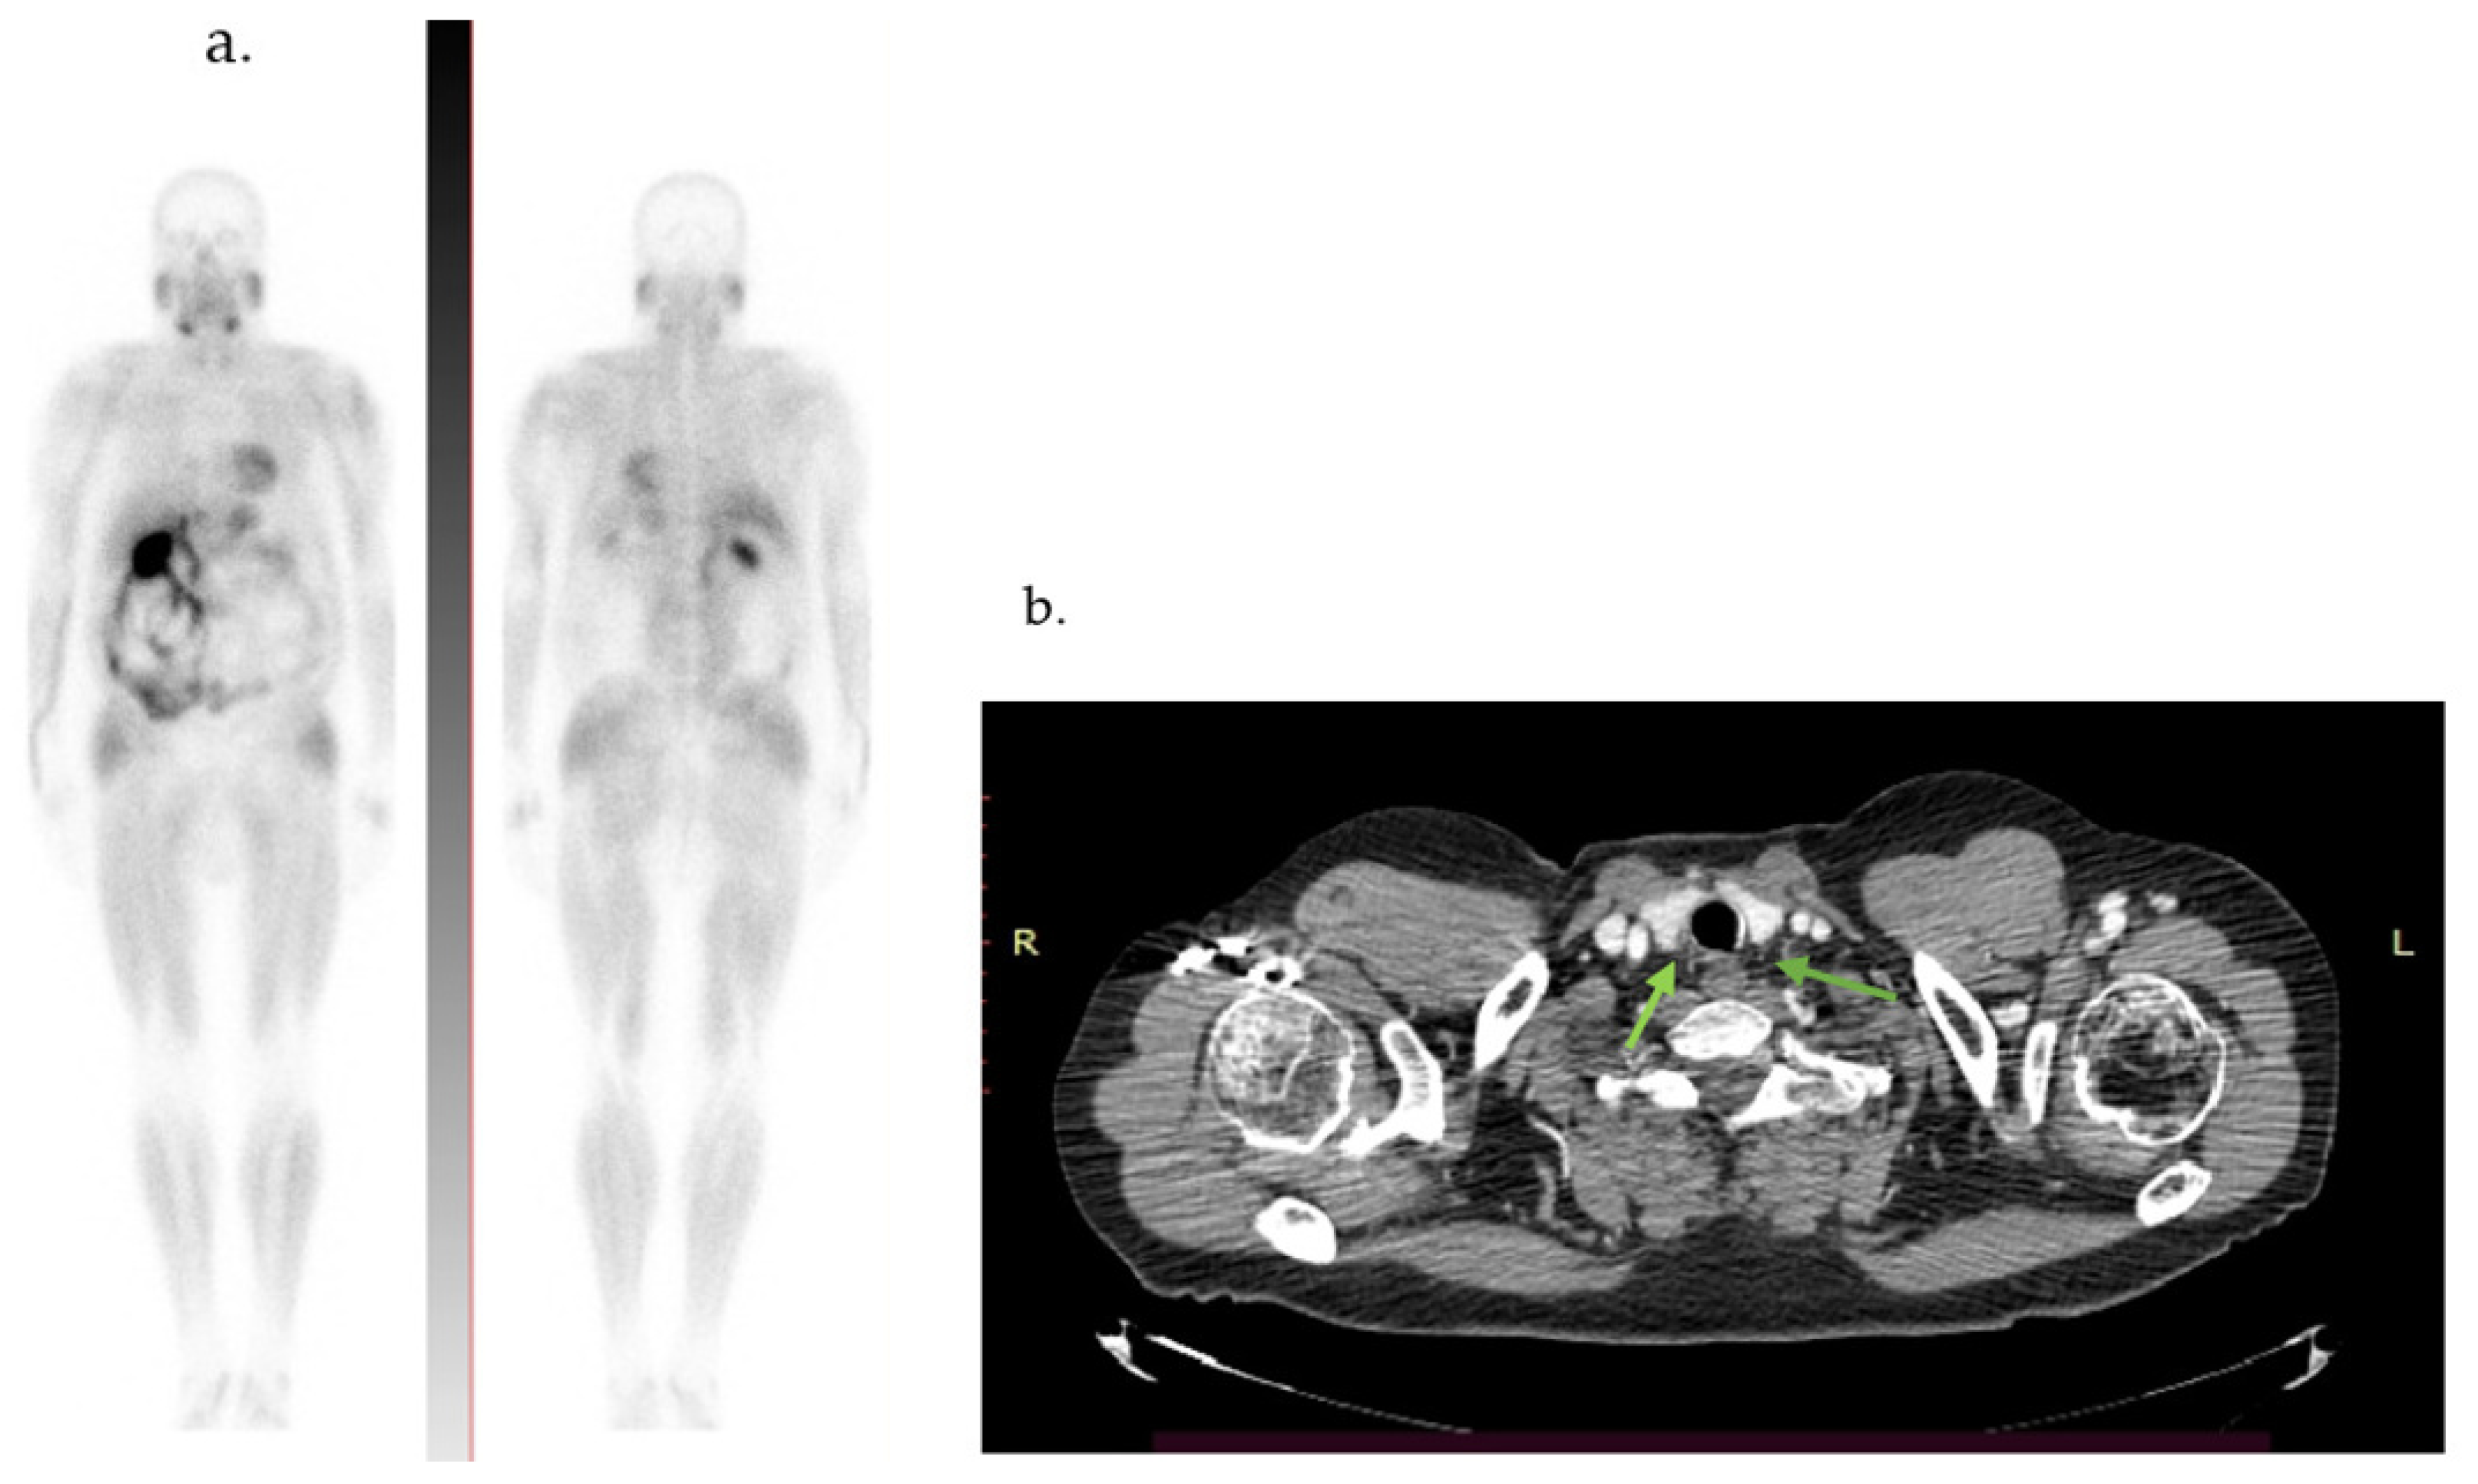

Three months after surgery, the whole-body 99mTc-MIBI scintigraphy and computed tomography (CT) scan were negative for any signs of recurrence, ectopic parathyroid lesions, or metastasis (Figure 5). During the 16-month follow-up, the patient’s PTH level decreased to 554 pg/mL, with slight fluctuations due to hypocalcemia (as shown in Table 2). He developed “hungry bones syndrome”, adequately managed with substitutive treatment.

Figure 5.

(a) 99mTcMIBI whole-body scintigraphy. (b) Cervical computed tomography: absence of any signs of recurrence 3 months after surgery (arrows).